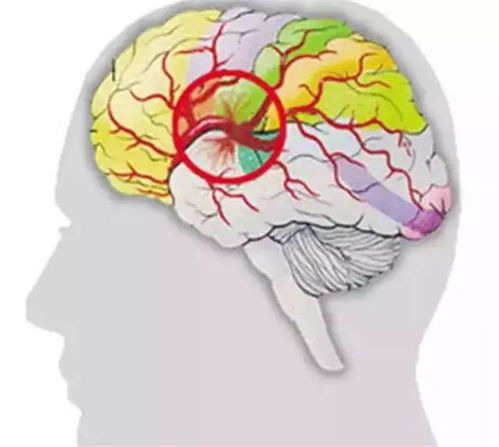

дкФГжжЬиЪтЧщПіЯТЃЌЕБбЊбЙМБОчЩ§ИпЃЌДяЕНЛђГЌЙ§НЯИпЕФНчЯоЪБЃЌР§ШчЪеЫѕбЙИпДя180mmHgвдЩЯЃЌЮвУЧЕФФдбЊЙмПЩФмЛсУцСйОоДѓЕФбЙСІЁЃетжжбЙСІВЛНіПЩФмЭЛЦЦФдбЊЙмЕФздЮвЕїНкМЋЯоЃЌЛЙЛсЕМжТФдбЊСїЙрзЂвьГЃдіМгЃЌДгЖјв§ЗЂФдЫЎжзКЭТФкбЙЩ§ИпЁЃетжжТФкбЙдіИпзДПіЛсЧПСвДЬМЄХЛЭТжаЪрЃЌЕМжТХчЩфадХЛЭТЃЌЭЌЪБАщЫцОчСвЭЗЭДЁЂЪгЮяФЃК§ЕШжЂзДЁЃЛМепПЩФмИаЪмЕНМЋДѓЕФВЛЪЪЁЃ

ИќЮЊбЯжиЕФЪЧЃЌЖёадИпбЊбЙзДПіПЩФмгеЗЂИќЮЊбЯжиЕФФдбЊЙмвтЭтЗчЯеЃЌШчФдГібЊЛђФдЙЃЫРЁЃдкетжжЧщПіЯТЃЌХЛЭТЭљЭљАщЫцзХвтЪЖеЯАЁЂжЋЬхТщФОЕШЩёОЯЕЭГжЂзДЕФГіЯжЁЃЮЊСЫзМШЗХаЖЯВЁЧщЃЌЛМепгІСЂМДНгЪмCTЛђMRIМьВщвдШЗеяЁЃ

бЊбЙЕФМБОчЩ§ИпЛЙПЩФмЖдФкЖњМАЧАЭЅЙІФмВњЩњгАЯьЁЃФкЖњЪЧЮЌГжШЫЬхЦНКтЕФживЊЦїЙйЃЌвЛЕЉЪмЕНбЊбЙЕФгАЯьЃЌЦфЙЉбЊзДПіПЩФмЛсЗЂЩњИФБфЃЌДгЖјЦЦЛЕЦНКтЙІФмЃЌв§ЗЂбЃдЮЁЃетжжбЃдЮЭљЭљАщЫцзХЖёаФКЭХЛЭТЃЌЦфжЂзДШнвзгыЖњЪЏжЂЛђОБзЕВЁЛьЯ§ЁЃЖдгкИпбЊбЙЛМепРДЫЕЃЌЕБГіЯжЯрЙижЂзДЪБЃЌгІЬсИпОЏЬшЁЃ

ЕБИпбЊбЙЛМепЕФХЛЭТжЂзДГіЯжЃЌВЂЧвбЊбЙДяЕНЛђГЌЙ§220/130mmHgЪБЃЌетБЛЪгЮЊвЛИіНєМБаХКХЁЃетжжзДПіПЩФмЬсЪОзХИпбЊбЙФдВЁЛђЮЃЯѓЕФЗЂЩњЃЌДцдкФд№оЁЂАаЦїЙйгРОУЫ№ЩЫЕШжТУќЗчЯеЁЃдкетжжЧщПіЯТЃЌЛМепгІСЂМДбАЧѓвНСЦОШжњЁЃ

ЖдгкГЄЦкИпбЊбЙЕФЛМепРДЫЕЃЌМДЪЙЫћУЧПЩФмвбОЪЪгІСЫИпбЙзДЬЌВЂднЪБЮоУїЯджЂзДЃЌЕЋЦїЙйЕФЫ№КІПЩФмШддкЧФЮоЩљЯЂЕиНјааЁЃНЕбЙжЮСЦашвЊбађНЅНјЃЌБмУтбЊбЙЕФжшНЕЃЌвдУтМгжиВЛЪЪЁЃЖдгкИпбЊбЙЛМепРДЫЕЃЌШєГіЯжХЛЭТАщЫцбЊбЙЯджјЩ§ИпЕФЧщПіЃЌгІСЂМДОЭеявдХХВщПЩФмЕФФдбЊЙмВЁБфЁЃдквНЩњЕФзЈвЕжИЕМЯТЃЌЛМепПЩЕУЕНИќЮЊОЋзМЕФеяЖЯКЭжЮСЦНЈвщЁЃ